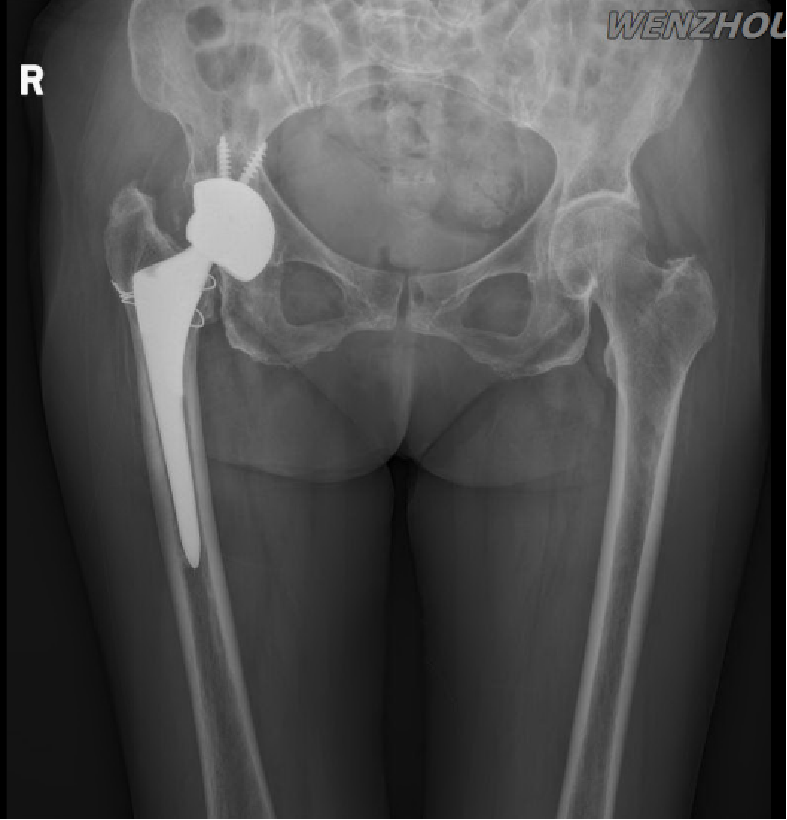

患者为79岁女性,因“跛行跌倒致右肩部及左腕部肿痛伴活动受限1天”入院。既往有多次骨折及多种基础疾病病史,5年前跌倒致右股骨颈骨折,行右侧全髋关节置换术;3年前扭伤致腰椎压缩性骨折,保守治疗;患有肝硬化、高血压、糖尿病、神经衰弱等疾病,长期不规则服药。本次受伤前右髋部疼痛,行走跛行,右下肢缩短约1.5厘米。

3、右人工髋关节置换术后,假体松动

2、右髋关节(THA)术后假体松动

考虑患者全身情况及局部骨量,决定待全身及局部骨量改善后2期行翻修手术。